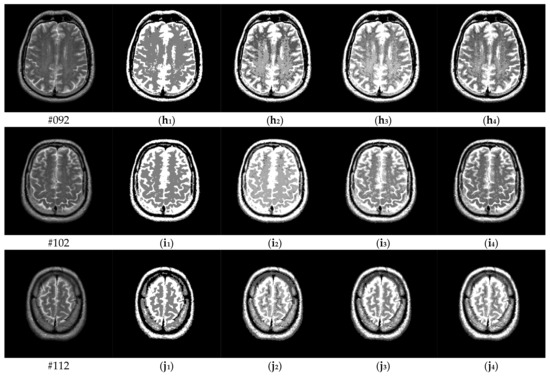

To verify the performance of the proposed algorithm, five representative multi-threshold segmentation algorithms are selected for comparative experiments. The five comparative experimental algorithms are: (1) image threshold segmentation algorithm based on particle swarm optimization (PSO), (2) image threshold segmentation algorithm based on bacterial foraging (BF), (3) image threshold segmentation algorithm based on adaptive bacterial foraging (ABF), (4) image threshold segmentation algorithm based on Nelder-Mead simplex (NMS), (5) image multi-threshold segmentation algorithm based on real coded genetic algorithm (RCGA) [43]. The number of thresholds is set to K = 2, 3, 4, and 5, respectively. Due to the limited space, we only show the segmentation results of the proposed algorithm in this paper. Figure 8 shows the segmentation results of Slice#022~#112 when the threshold K = 2, 3, 4, 5. Intuitively, the proposed algorithm can better segment each region of the experimental image, and the continuity of different regions is well guaranteed. At the same time, the visual effects are satisfactory.

Figure 8.

Segmentation results obtained by the proposed algorithm for brain slices #022~#112; (a1–j1) display the results of 2-thresholding; (a2–j2) display the results of 3-thresholding; and (a3–j3) display the results of 4-thresholding; (a4–j4) display the results of 5-thresholding.